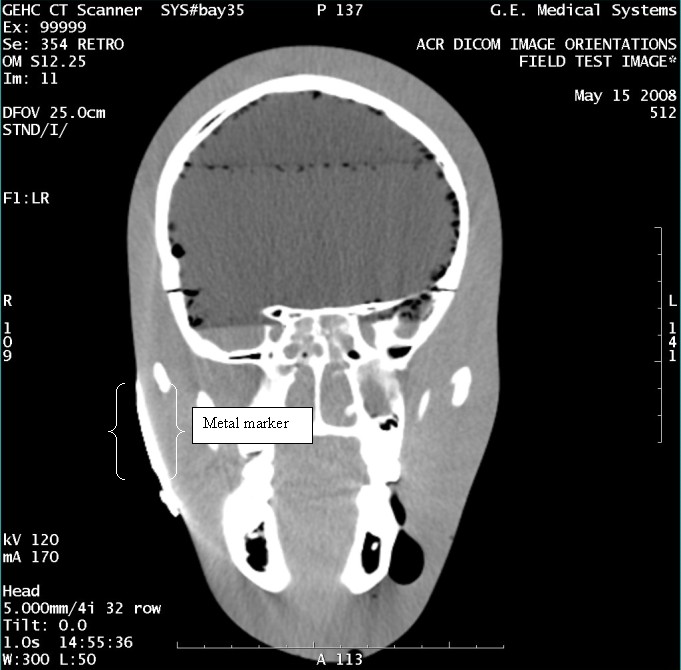

- With the support of the site personnel, examine the images sent

to the Review Station (i.e., 12 series, each with 1 image) and compare

their orientation to the images in this document.

- Each image contains a metal marker on the phantom's right cheek.

- Each image in this document contains a description of the expected

orientation of the metal marker (i.e. to prove Left and Right) as

well as the Posterior and Anterior orientation description.note:

The sample images included in this document use “R”, “L”, “P”, and “A” for “Right”, “Left”, “Posterior” and “Anterior” orientation. The Hospital Review Station may use a different style of annotation. The style used is not relevant to this procedure.

Figure 12. Exam 99999, Series 354